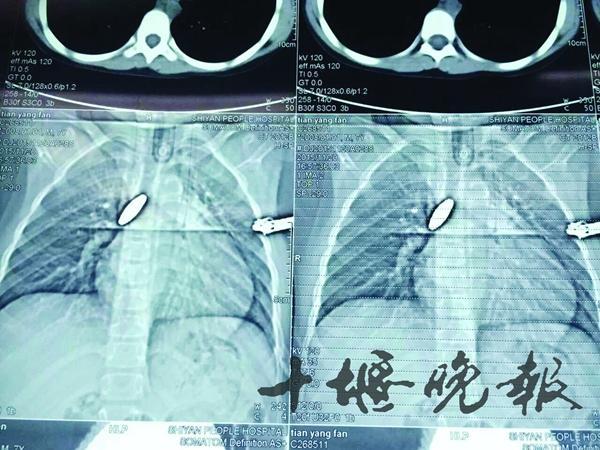

3、异物在食管内停留时间过长,或尖锐异物的直接损伤,而发生食管炎、食管脓肿、食管穿孔、纵隔感染、食管器官瘘、化脓性胸膜炎等并发症。还可出现发热、脱水、呼吸困难及全身中毒症状。

4、有时尖锐异物(小骨碎片或鱼骨刺)可直接穿透食管壁,穿破主动脉或心包,引起消化道大出血或心包化脓,有极大危险性。